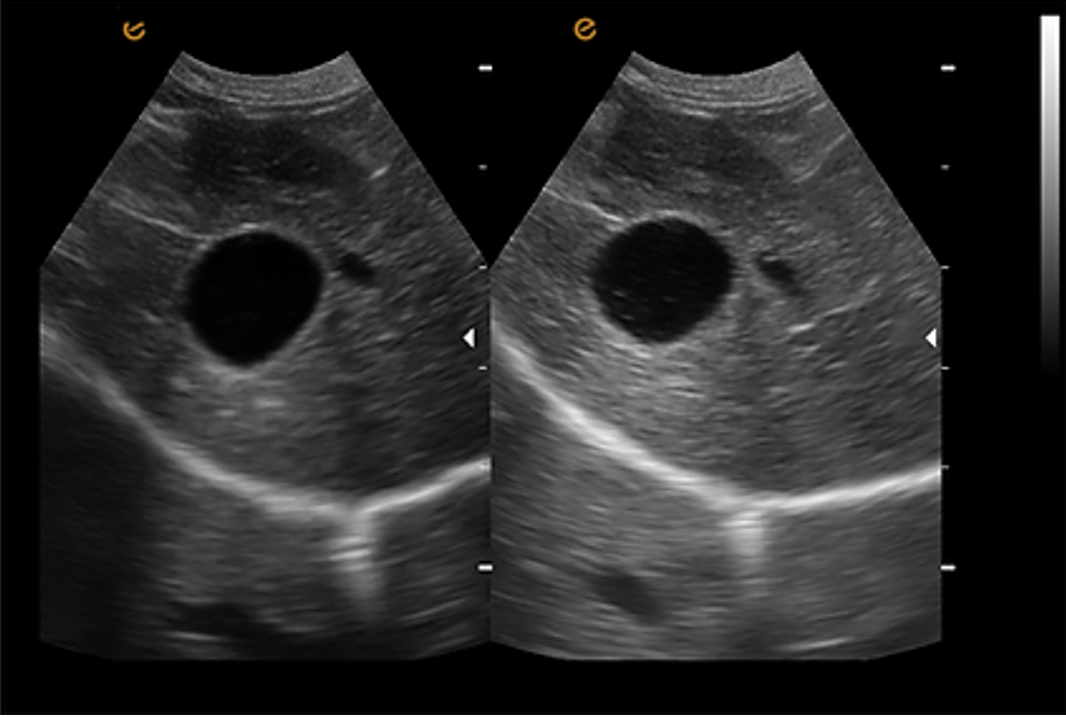

eTSI: การถ่ายภาพเฉพาะเนื้อเยื่อ การถ่ายภาพเฉพาะเนื้อเยื่อ (Tissue Specific Imaging) เป็นเทคโนโลยีที่ปรับอัตโนมัติตามสื่อที่เปลี่ยนแปลงไป (Transition Media) เพื่อให้ได้ความละเอียดของภาพที่ดีที่สุด |